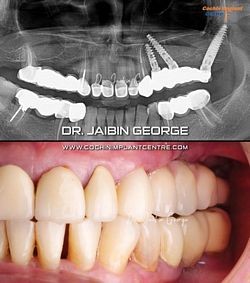

Case No: 19